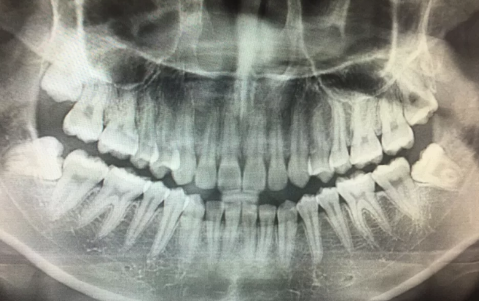

1、反復炎癥:智齒出牙不完整,齦冠覆蓋后側部分形成冠周袋。不注意個人衛生,局部軟組織往往會發炎,出現疼痛癥狀,所以需要拔掉智齒才能有效改善。

2、影響鄰近牙齒:如果牙齒生長位置不正確而擁擠,就有可能對鄰近牙齒造成損害,使咀嚼功能嚴重受損,因此需要拔除智齒。